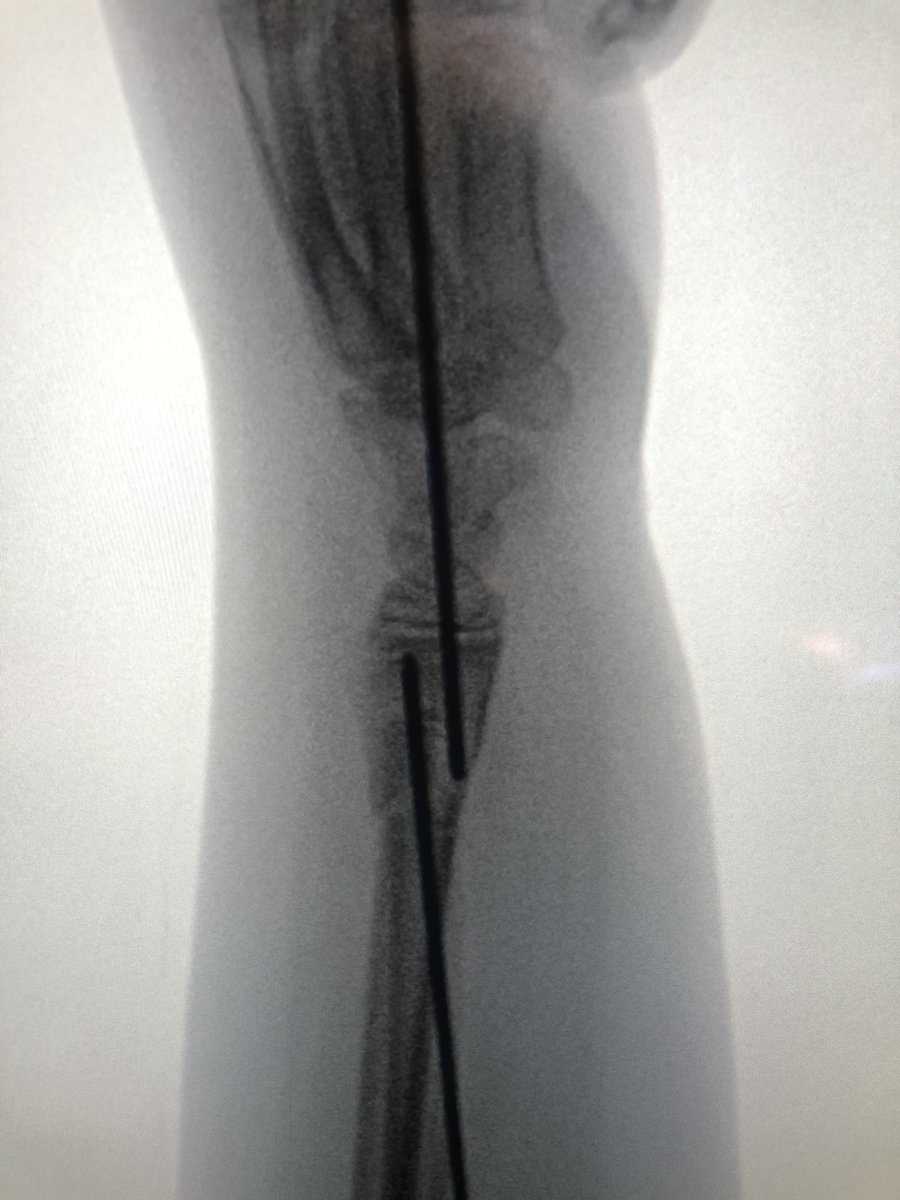

[3/4] This is my reduction, manually on distal fragment, with my other hand on threaded wire pulling it radially, using it as joystick. Once lined up, since distal wire already in and pointing in correct direction, all my resident has to do is fire wire into proximal fragment.

[4/4] I didn’t I think one wire was going to be enough, so I removed joystick and then placed another smooth wire proximal to distal; there wasn’t much room in there because trying not to get the physis. Cast, then pins pulled in clinic at 4 weeks. Xrays done at 2, 4, 8 weeks.